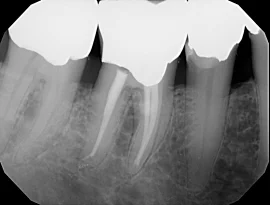

A ROOT CANAL CAN SAVE YOUR TOOTH

Once upon a time, if you had a tooth with a diseased nerve, you'd probably lose that tooth. Today, with a special dental procedure called root canal therapy you have the option to save that tooth. Inside each tooth is the “pulp” which provides nutrients and nerves to the tooth, it runs like a thread down through the root of the tooth. When the pulp is diseased or injured, the pulp tissue dies. If you don't remove it, your tooth gets infected and can cause an abscess, resulting in potential loss of the tooth. After the pulp is removed, the root canal is cleaned and sealed off to protect it. Normally a crown is required to be placed over the tooth to help make it stronger and ensure that it lasts for years to come.

Most of the time, a root canal is a relatively simple procedure with little or no discomfort. Best of all, it can save your tooth and preserve your smile!